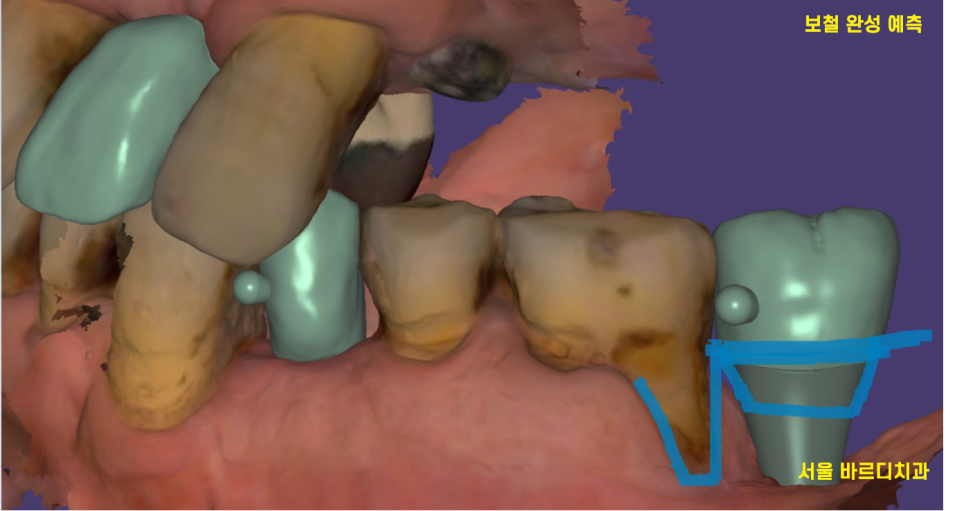

23.11.14

상일동역 근처 치과는

임플란트 처음부터 끝까지 디지털 기술을 활용합니다.

보철을 완성할 때도

스캔 기술을 활용하여 입안 구석구석 사진을 찍어

재현합니다.

보철이 들어갈 부분을 예측하면서

환자분의 입안 상태를

돌려보고 또 돌려봅니다.